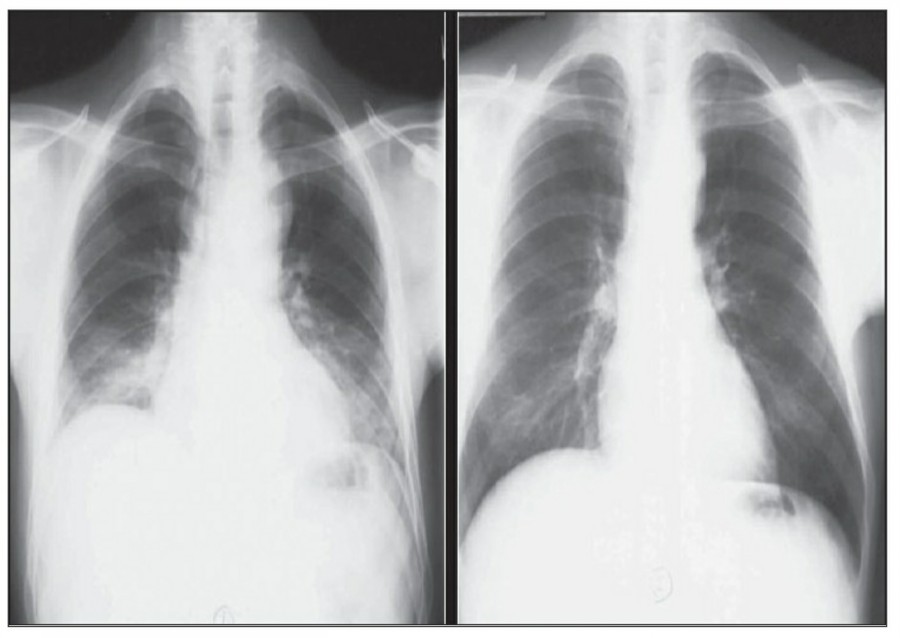

CABG를 받은 환자에서 lower lobe atelectasis는 흔한데, 주로 왼쪽에 잘 나타나며 수일 내에 별다른 합병증 없이 회복된다. mediastinum도 약간 확대되어 보일 수 있는데, 만약 그 diameter가 많이 증가한다면 mediastinal hemorrhage 등을 시사할 수 있다. CABG 시행 후 약간의 좌측 pleural effusion은 있을 수 있지만 그 양이 많거나 증가한다면 respiratory compromise를 줄이기 위해 intervention이 필요할 수 있다. 따라서 이전의 사진과 비교를 해서 pleural effusion 양의 변화가 있는지 확인이 필요하겠다.